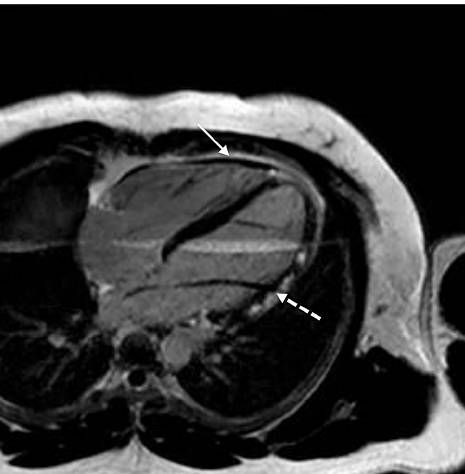

心脏核磁

SSFP gradient-echo white blood cine images in modified four-chamber view

Black-blood fast SE sequence without fat suppression

cine (SSFP) CMR ,nonspecific overall thickening of the pericardium (black

arrow)

增厚的心包,胸水缩窄的症状

1个月激素治疗后,心包厚度正常

•CMR with intense delayed enhancement (red arrows) of the pericardium (left).

•After 6 weeks of prednisone therapy, the delayed enhancement was reduced (right).